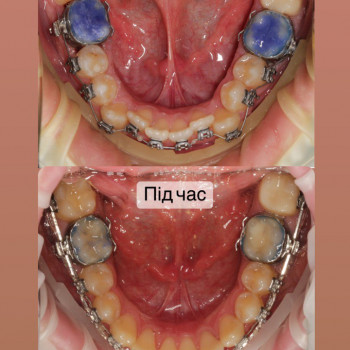

| Ортодонтия | |

| Установка брекетов | |

| Металлические брекеты | |

Перший крок - це консультація ортодонта, Ви зможете дізнатись відповіді на запитання які Вас хвилюють. Перед постановкою брекетів усі зубки мають бути здорові, якщо ми бачимо карієс, його потрібно полікувати. Також потрібно зробити рентгенівські знимки для діагностики. За цей час, коли ми готуємо зуби до постановки брекетів, Ви зможете налаштуватись морально, звикнути з думкою що Ваша посмішка засяє новими барвами. На сьогоднішній час носіння брекетів являється престижним!